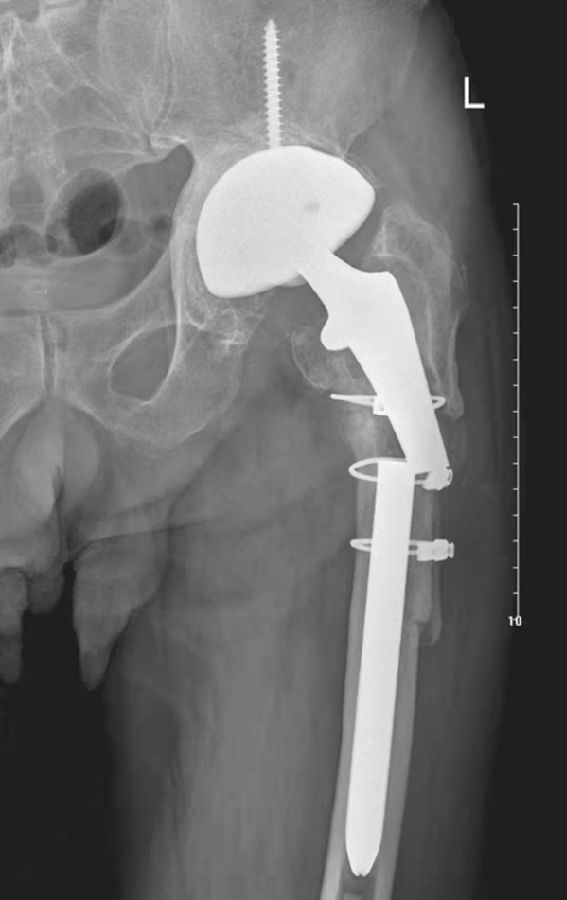

图3 无菌性松动

平片,示右侧髋臼杯周围骨质吸收,髋臼杯松动并向上内侧移位